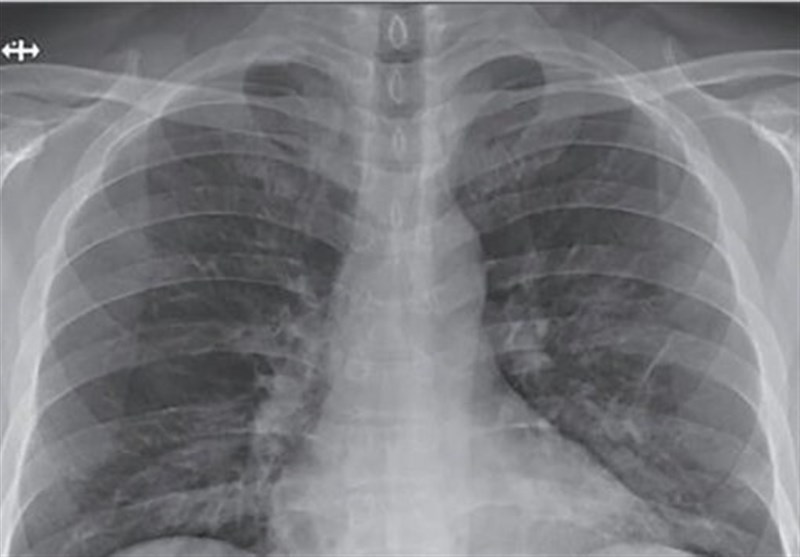

کرونا چه بلایی بر سر ریه‌ها می‌آورد؟

کروناویروس‌ به خاطر وجود شاخک‌های تاجی شکلی که بر روی سطوحش وجود دارد، با این نام شناخته شده و می‌تواند سبب بروز کووید 19 شود. این ویروس یک عفونت ویروسی واگیردار است که در ابتدا گلو و سپس ریه‌ فرد مبتلا را درگیر می‌کند.

به گزارش گروه رسانه های خبرگزاری تسنیم، کروناویروس‌ به خاطر وجود شاخک‌های تاجی شکلی که بر روی سطوحش وجود دارد، با این نام شناخته شده و می‌تواند سبب بروز کووید 19 شود. این ویروس یک عفونت ویروسی واگیردار است که در ابتدا گلو و سپس ریه‌ فرد مبتلا را درگیر می‌کند.

هر کدام از ریه‌ها از چند بخش تشکیل شده است، در حالت عادی هنگامی که تنفس می‌کنیم هوا آزادانه درون نای و لوله‌های تنفسی حرکت می‌کند و سپس وارد کیسه‌های هوایی می‌شود. این کیسه‌های هوایی خاصیت ارتجاعی دارند و هر کدام از آنها ساختاری مانند یک بادکنک کوچک دارد که کار تبادل اکسیژن تازه و کربن دی‌اکسید در این محل و بین رگ‌ها و کیسه‌های هوایی انجام می‌شود. لایه موجود در مجاری تنفسی بیشتر میکروب‌هارا به خود جذب می‌کند.

در بدن یک فرد سالم مژک‌هایی در مجاری تنفسی وجود دارند که مدام میکروب‌های درون مجاری تنفسی را به بیرون هدایت می‌کنند و در نهایت فرد با یک سرفه آنها را از بدن خارج می‌کند. از طرفی سلول‌های دستگاه ایمنی بدن میکروب‌ها و ویروس‌هایی که به کیسه‌های هوایی رسیده اند را نابود می‌کند اما وقتی دستگاه ایمنی بدن ضعیف باشد،‌ مثل موارد ابتلا به کرونا ویروس، ویروس‌ها می‌توانند دستگاه ایمنی بدن فرد را احاطه کرده و تحت تاثیر قرار دهند. در چنین حالتی کیسه‌های هوایی ملتهب شده و دستگاه ایمنی شروع به حمله به ویروس‌های در حال تکثیر می‌کند و در نتیجه این التهاب کیسه‌های هوایی پر از مایع می‌شوند و کار تبادل اکسیژن سخت می‌شود.

بنابر اعلام کانال خبری سازمان نظام پزشکی، عفونت ویروسی ایجاد شده می‌تواند حتی هر دو ریه فرد مبتلا را آلوده کند که به دنبال بروز این عفونت تنفس فرد سخت شده و درد سینه احساس خواهد کرد.

سرفه،‌ تب و لرز، پریشانی، سر درد، درد و کوفتگی بدن، احساس خستگی از علائم عفونت ریه است، اما عوارض این مشکل گاها جدی‌تر هم می‌شود. وقتی تنفس برای فرد مبتلا به بیماری سخت شود نارسایی تنفسی ایجاد شده و در آن شرایط فرد برای تنفس نیاز به دستگاه‌های کمک تنفسی یا ونتیلاتور خواهد بود. البته شدت بروز علائم در هر فرد وابسته به عوامل مختلفی همچون سن، شرایط ایمنی بدن و... دارد.